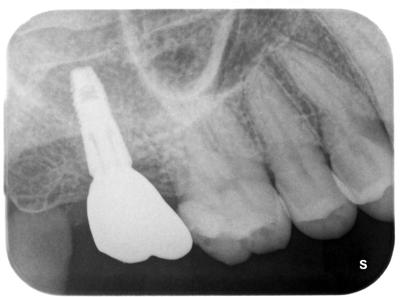

右上7部へのインプラント治療。

使用インプラントはアストラテックインプラント(スウェーデン)。

上顎洞が低く十分な骨がないため、自家骨+バイオスを用い、ソケットリフトによるサイナスリフトを行っている。